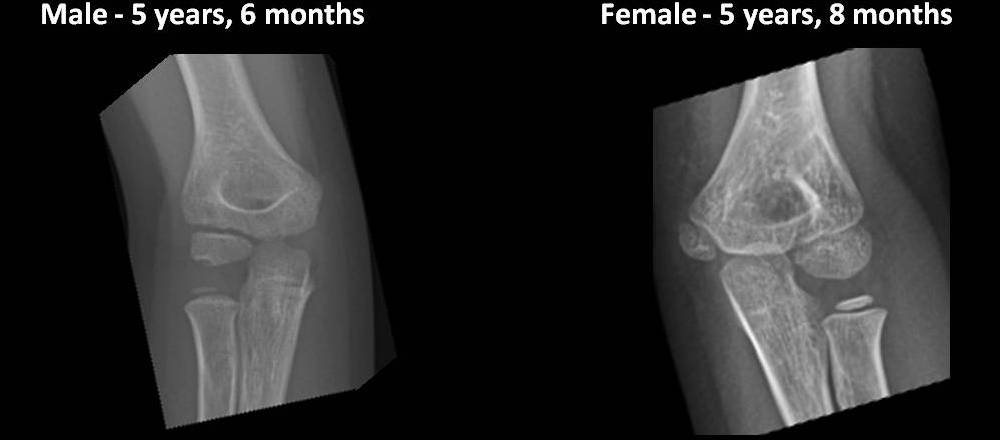

Elbow Ossification Centers

The ages at which the elbow ossification centers appear are highly variable. There is marked gender difference with girls developing up to 2 years before boys. However, the order of appearance of the ossification centers is highly reliable and follows the CRITOE mnemonic: Capitulum, Radial head, medial (Internal) epicondyle, Trochlea, Olecranon, and lateral (External) epicondyle. Pay attention to the appearance and maturation of the normal ossification centers as you scroll through the images below.

*Each image in this exhibit represents a unique patient radiographed at CHP of UPMC between 07/01/12 and 06/30/13